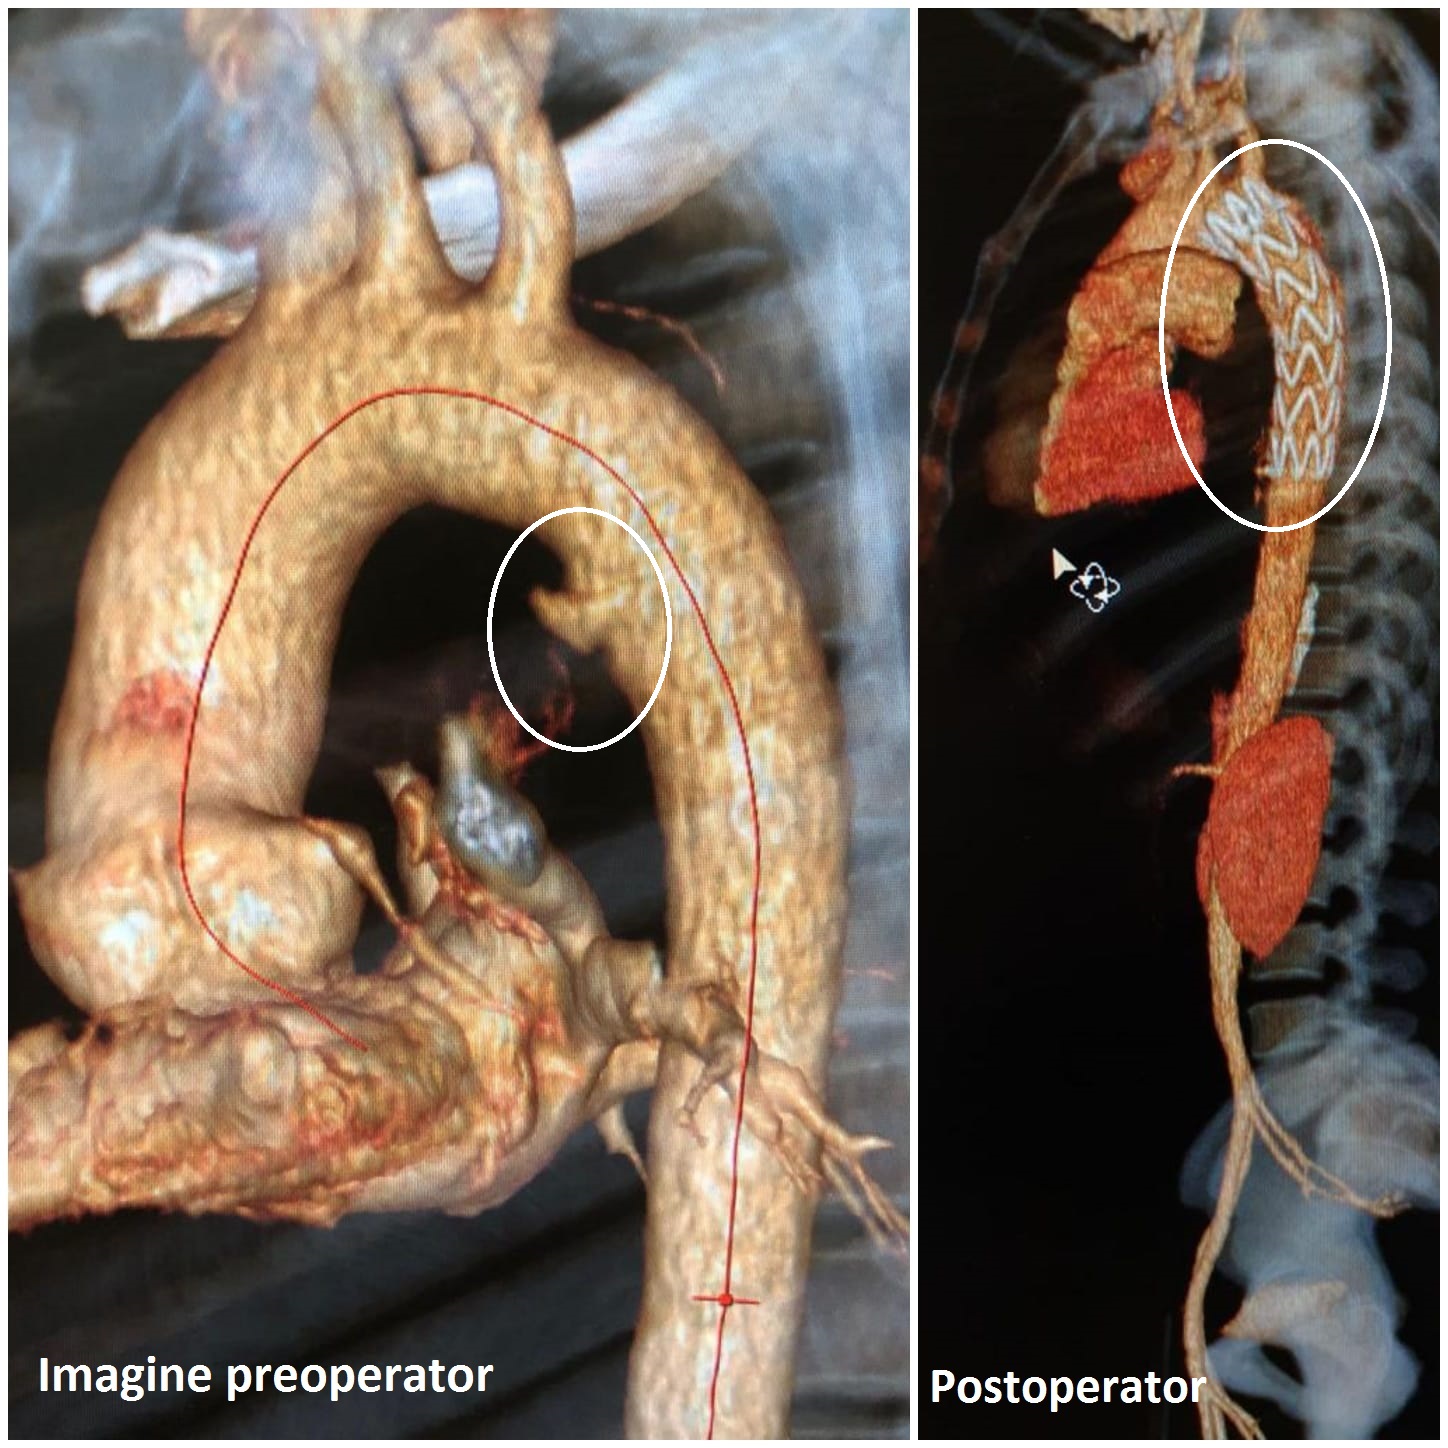

Pacientul a ajuns cu politraumatism la Unitatea de Primiri Urgențe, a fost examinat la computerul tomograf cu substanță de contrast, pe bază căruia s-a găsit leziunea aortică, o rană care, deși abia vizibilă, l-ar fi costat viața. Medicii, puși în fața unui asemenea diagnostic grav, au luat o decizie în regim de urgență și i-au montat, pe aortă, printr-un procedeu revoluționar, o proteză potrivită. "Pacientul avea o fisură de aortă toracică, și am decis montarea, în Urgență, a unei endoproteze de aortă toracică pe cale femurală stângă, pentru acoperirea zonei de fisură aortică", spune dr.

Dragoș Trandafir, coordonatorul secției de Chirurgie Vasculară din cadrul Spitalului Universitar.

"Fisura era pe aortă descendentă și pentru că exista riscul să se rupă mai rău, am decis montarea protezei, aceasta fiind procedura cea mai puțin riscantă pentru pacient. Practic, am montat un manșon, să-i spunem așa, pe interiorul vasului fisurat, pentru a preveni o ruptură. Este o intervenție minim invazivă, dar cu anestezie generală, ca pacientul să stea liniștit și bine monitorizat.

Intervenția a durat mai puțin de o oră", a declarat dr. Bogdan Dorobăț, coordonatorul Compartimentului de Radiologie Intervențională din cadrul SUUB.